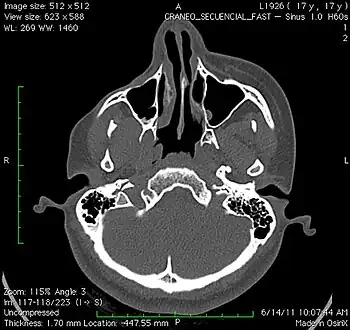

An axial CT scan of a 17-year-old girl with Parry–Romberg syndrome, showing severe loss of subcutaneous tissue and muscle of the right side of the face, with no apparent involvement of the facial bones